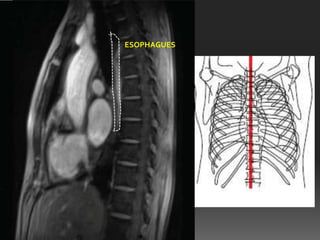

ESOPHAGUS

ESOPHAGUES